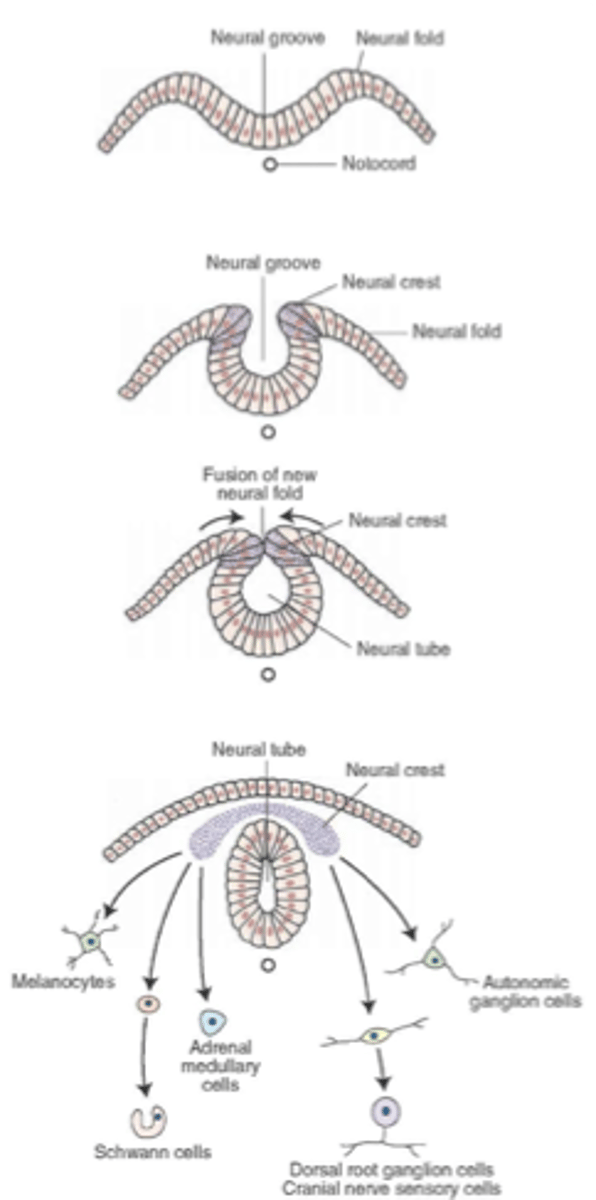

what are the cells that appear along the edge of the neural plate as it elevates?

neural crest cells

what are ganglia, meninges, and Schwann cells derived from?

these arise from the neural crest cells

the fusion of the neural folds begins in the __________ region then proceeds ___________ and __________ to form the neural ________

cervical, cranially, caudally, tube

the (caudal/cranial) neuropore will normally close on day ____ before the (caudal/cranial) neuropore which closes on day ____

cranial, 25, caudal, 28

the narrow (caudal/cranial) portion of the neural tube will form the spinal cord while the broad (caudal/cranial) portion forms the brain vesicles

caudal, cranial